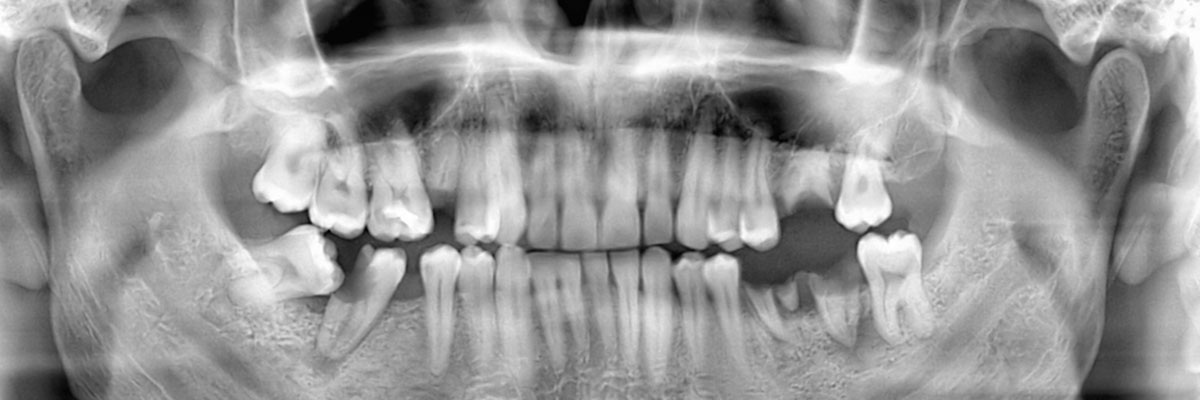

Wisdom teeth extraction can help to relieve pain in a patient's teeth that results from the wisdom teeth causing crowding issues or growing incorrectly. There are many different reasons you may need to extract your wisdom teeth. Wisdom teeth extraction removes the third set of molars in the back of your mouth.

"Wisdom teeth" is the colloquial term for the third set of molars that sit in the back of the mouth. They are called such because they come between the more "mature" ages of 17 and 21. The emergence of wisdom teeth can be uncomfortable, even if they are emerging correctly. Wisdom teeth do not always necessitate extraction. On the contrary, properly aligned wisdom teeth may assist in chewing.

However, if there is no adequate space for the wisdom teeth to emerge or if the teeth are coming through in the wrong position, they may become impacted (or trapped in the jaw or under the gums). This may cause cysts, damage to neighboring teeth, gum disease, infection, pain, tooth, decay, and tumors. A dentist needs to monitor the patient's wisdom teeth and determine the best course of action.